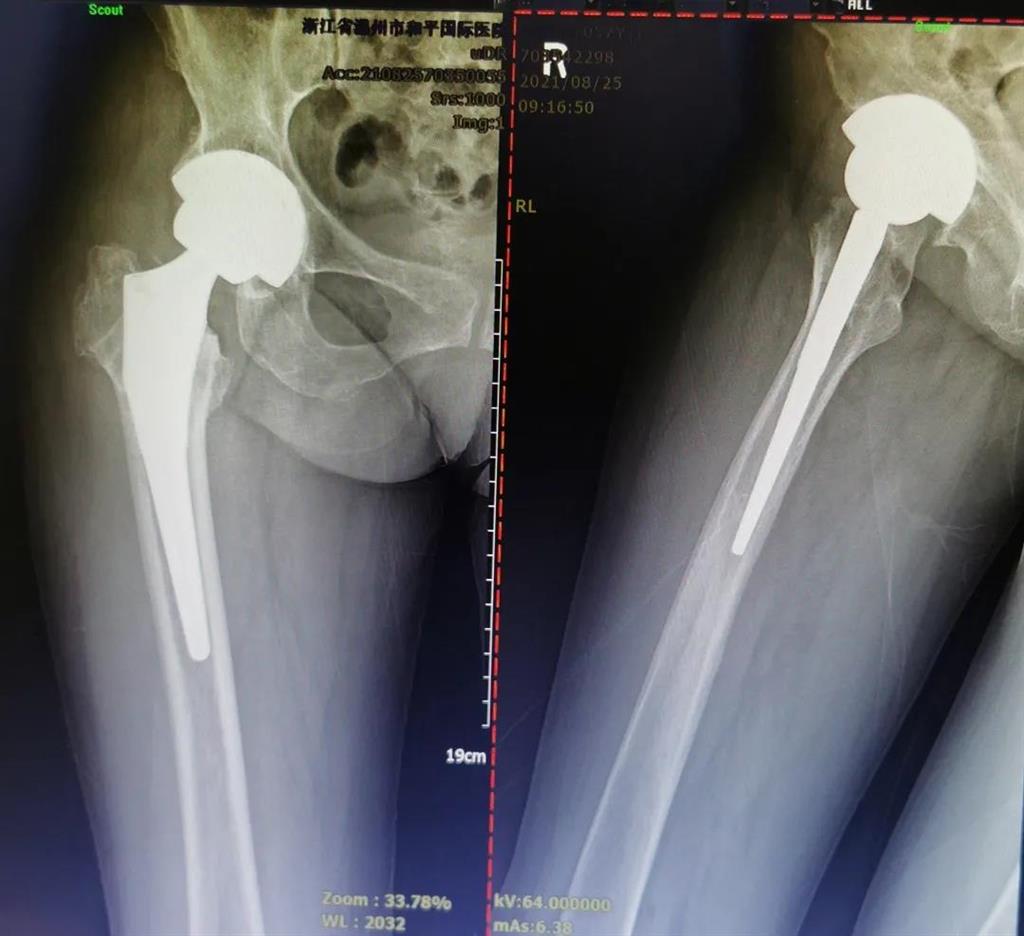

手術(shù)很成功!李女士術(shù)后第二天便可下地進(jìn)行簡(jiǎn)單的鍛煉了。

兩個(gè)月后,李女士的腿已與常人無(wú)異,苦纏2年有余的病痛,終于徹底消散。

(△做完“右股骨頸全髖關(guān)節(jié)置換術(shù)”后的影像)